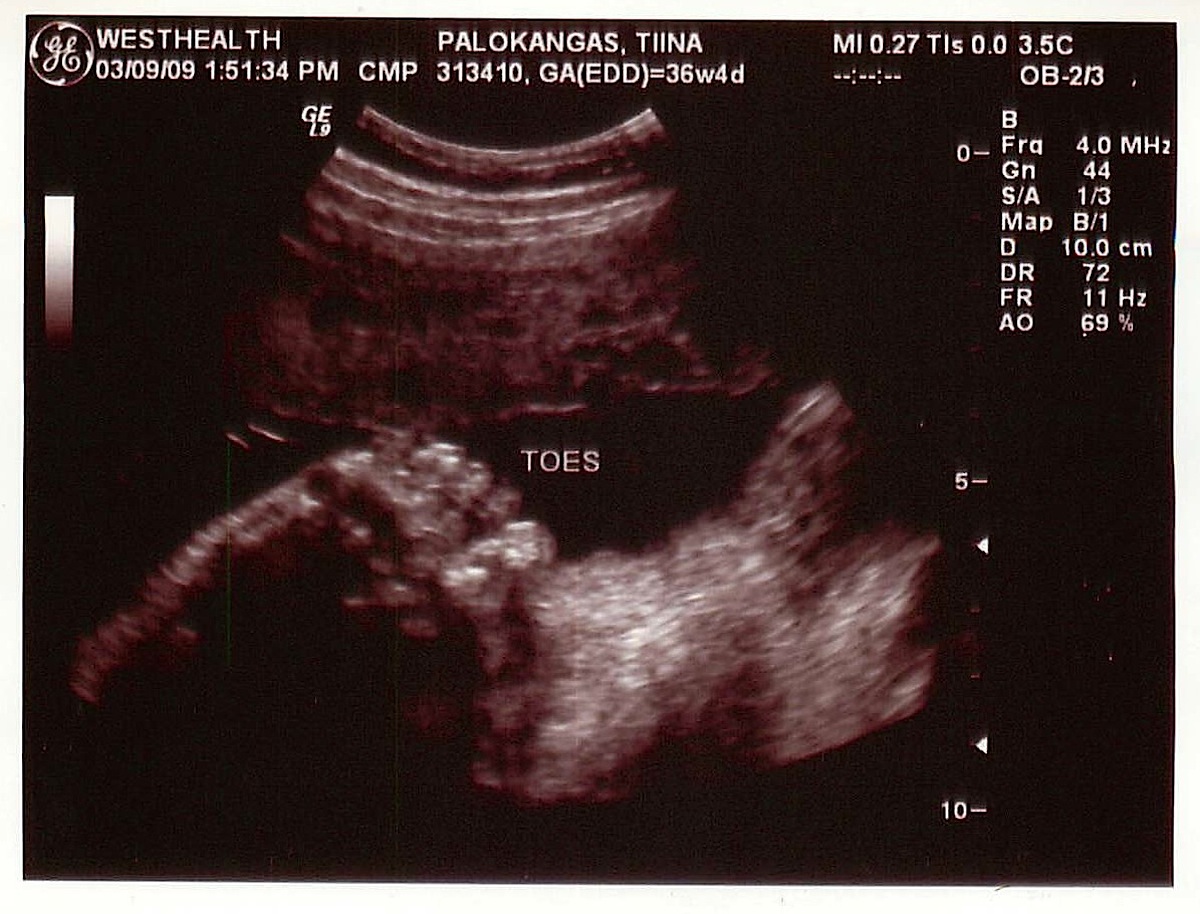

Ultrassa Eelikin erotti Masasta jo paljon enemmän kuin viime kerralla (marraskuussa). Profiili oli tuttu, melko turpeahuulinen ja nöpönenäinen. Masa oli jo tosi iso, yli kolmekiloinen (!) ja se puuhaili siellä mahassa vaikka mitä! Se haukotteli, aukoi suutaan ja massutti. Sitten se imi sormia, ensin yhtä ja sitten montaa yhtä aikaa. Sitä oli aika hauska katsella. Sitten laskettiin viisi varvasta toisesta jalasta. Toisesta ei laskettu. Eeliä alkoi Masan puuhia seuratessa mietityttää, että ”äiti, oletko sinä synnyttänyt isinkin?” Perhesuhteita käytiin läpi eilen, kun Eeli kesken välipalan syönnin yhtäkkiä kysyi äitiltä, että ”onko Veikko-pappa ja Maire-mummu sun isi ja äiti?”. Sitten me piirrettiin alkeellinen sukupuu, mitä Eeli piti tosi kiinnostavana ja katseli sitä pitkään. Isin vanhemmat piti merkitä ”Eelin mummuksi ja Eelin papaksi”.

”Digi-Masa” näyttää kuvissa kauniilta.

having seen her face and feet in reality – these ultrasound shots are amazingly accurate!